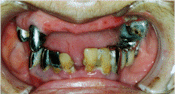

寝たきりの方の入れ歯と口腔内 |

しろっぽいところはバイキンの塊。 口腔の機能が悪いと自浄作用も落ちて汚れが繁殖しやすい |

話す、食べることがないと口腔内の環境はとたんに悪くなる。 |

嚥下の機能低下があるとこれらのバイキンが気管を通して肺に入ってしまう。 |